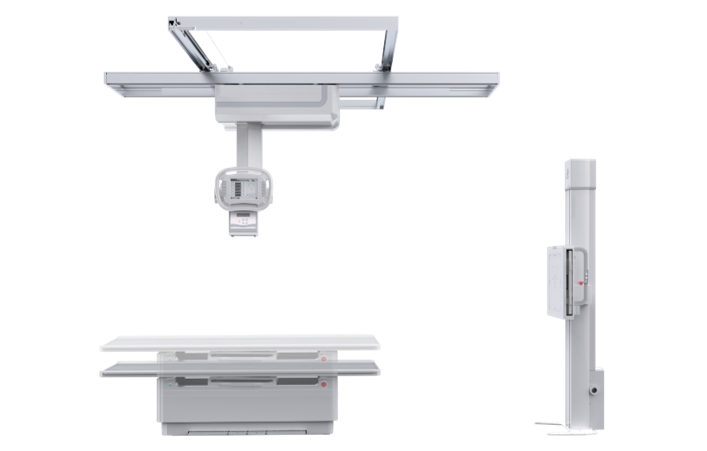

PLD7600

多功能悬吊动态DR

一机多用 PLD7600

● 智能升降床体

智能升降床设计,便于老、幼、病残或行动不便者上下床,给患者以及医护人员带来更舒适的检查体验,智能化程度极高。

● 双向自动跟踪

探测器与球管双向自动跟踪,无需手动校正,多角度高精度实时同步;

胸片位、床上位电动转换,一键到位。

● 低位摄影

球管及胸片架可大范围纵向移动,平板探测器中心最低离地35cm,轻松满足膝关节、踝关节等低位摄影的要求。

● 特殊角度摄影

牛头可全角度旋转,满足全身各部位的应用,特有的倾斜投照位,可满足特殊病人的临床应用。

● 手动电动一体化

悬吊配备手动模式与电动模式,沿天轨横纵移动时可选手动或电动,满足不同医护人员使用习惯。

● 自动对中

球管自动对准探测器中心点,无需手动校准,便捷高效。

● 自动控制曝光

无需手动调节,系统准确地控制射线剂量,获得适当的感光量,保证优秀的影像效果。

● 图像拼接

系统可以识别曝光图像,无需设置识别点即完成精准拼接,呈现大范围完整影像。

● 平板在线充电技术

胸片架或摄影床的片盒系统内置在线充电口,快速充电,持久续航。